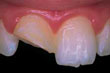

Haljennut tai murtunut hammas - Haljennut tai murtunut hammas tulisi hoitaa välittömästi vakavempien vaurioiden välttämiseksi.

![]() | Haljennut etuhammas |